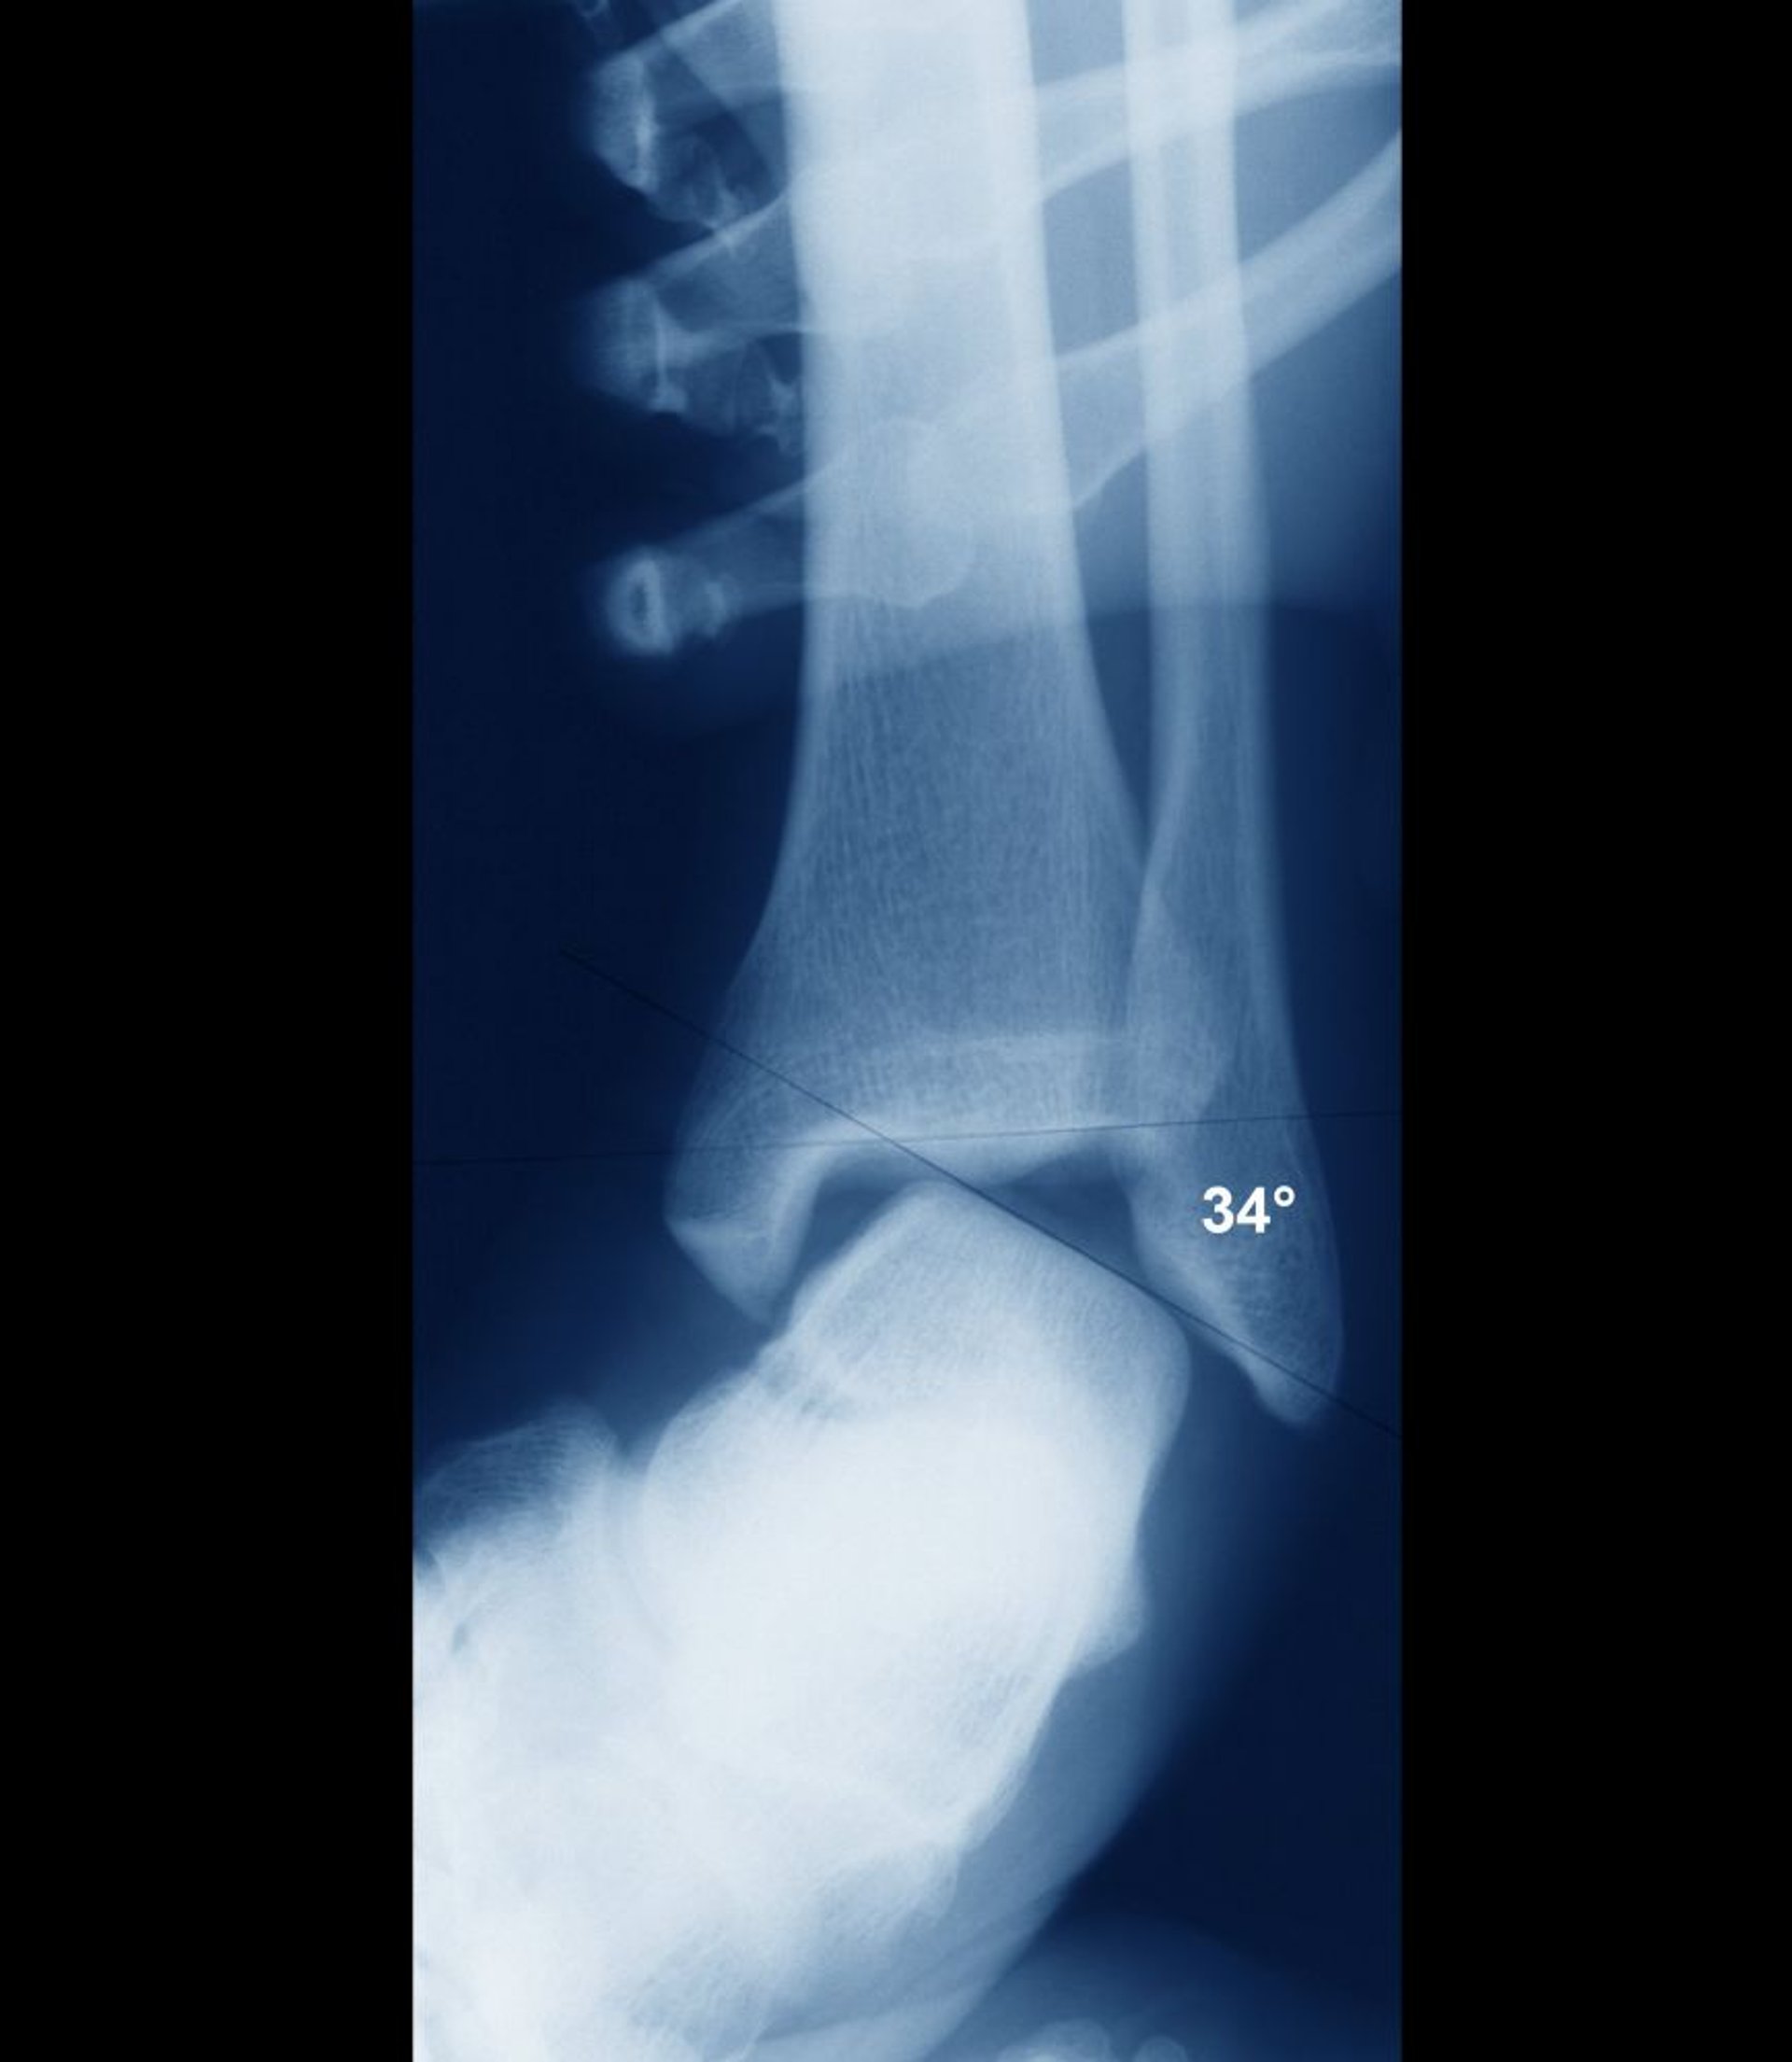

Entorse de la cheville avec instabilité

Si la cheville est stable, les surfaces intra-articulaires de l'astragale et du tibia doivent être parallèles. Ici, elles sont largement désalignées, ce qui indique une instabilité articulaire importante. L'instabilité aurait été clairement évidente cliniquement et l'instabilité est habituellement évaluée cliniquement sans besoin de radiographies.